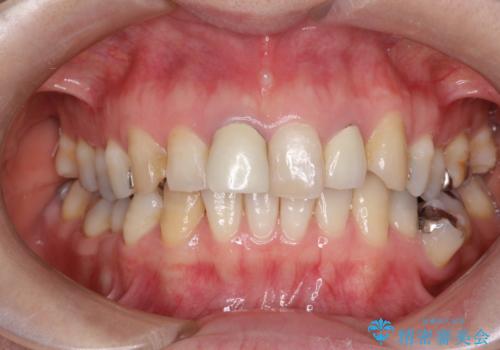

- 他院で装着された保険の前歯のかぶせ物が、他と歯と馴染まないので、自然な歯にしたいとのことで来院されました。

右上の1番目の歯の保険のかぶせ物と金属の土台を、ファイバーコアとオールセラミックにて再補綴する計画としました。

形態も色調もまわりの歯とは、調和がとれておらず、目立っていました。